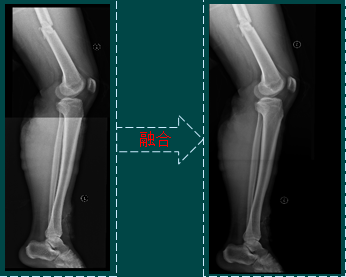

四肢

图像拼接

图像拼接(背景)

图像拼接是将数张有重叠部分的图像(可能是不同时间、不同视角或者不同传感器获得的)拼成一幅大型的无缝高分辨路图像的技术。

图像拼接(结果)